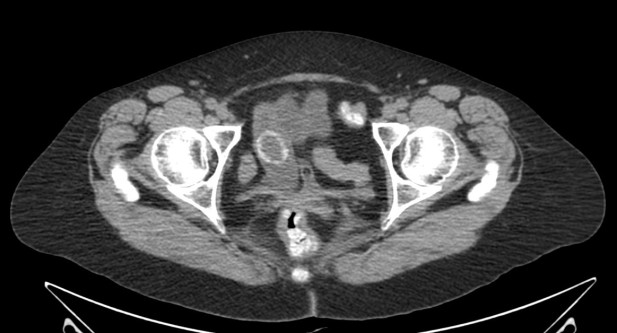

HERNIAS.

Constituyen la primera causa en pacientes sin antecedentes quirúrgicos abdominales. Pueden ser hernias externas o internas:

- Externas: se producen a través de un defecto en la pared y puden ser inguinales, femorales, del obturador, umbilicales, de Spiegel, lumbares y laparotómicas. En la tomografia, se observan las asas en el orificio herniario con dilatación de asas proximales y colapso de las distales al mismo. Existe alto riesgo de estrangulación (valorar los signos de isquemia).